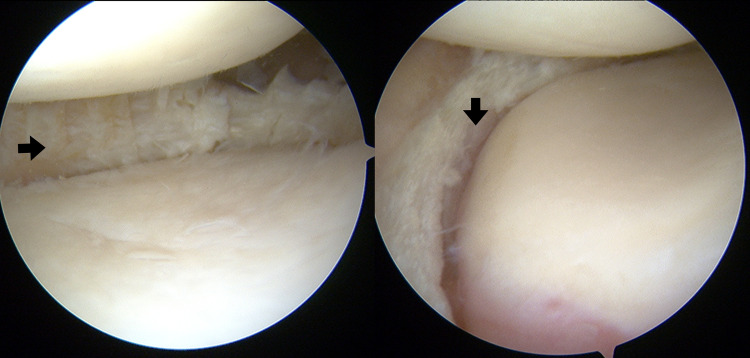

Purpose of review: Meniscectomy alters knee function and known to be associated with an increased incidence of knee arthritis. Several methods and materials have been tried to replicate the function of a meniscus. One is a polycarbonate-urethane synthetic medial meniscus implant labeled as NUsurface. It is a non-anchored implant that is meant to replace the native meniscus. This article is intended to give an overview of the NUsurface implant and the experience to date.

Recent findings: The NUsurface implant is not intended to be a substitute for arthroplasty but has indications similar to meniscal allografts. It has had both prospective double armed and single armed prospective studies. Follow up at the 2-year mark has shown the implant can be successful in decreasing patients' pain and improving function. However, the reoperation rate has been high with a little over a 1/3 requiring an additional procedure and 30% requiring implant exchanged. With improved surgical technique and knowledge of contributing anatomic variables, the reoperation rate has been decreased by half. The synthetic medial meniscus implant NUsurface is able to improve the quality of life in select patients that are symptomatic after meniscectomy. The reoperation rate is of concern but it is decreasing as we refine the variables contributing to the high rate.